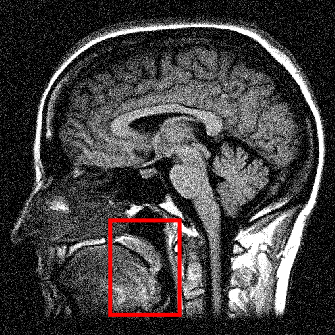

We display the noisy image and the reconstructed images from these three denoising methods in Fig. 8 111 Image retrieved from http://radiopaedia.org/ by Frank Gaillard.. To better understand the performance, we zoom in the selected part of the image and display them in Fig. 9.

Refer to caption

(a) Noisy

(b) Anisotropic TV

(c) TFV, α=1.3𝛼1.3\alpha=1.3

(d) TV-TFV, α=1.3𝛼1.3\alpha=1.3

Figure 8: Denoising results for models with different regularities. Here α𝛼\alpha denotes the fractional order of derivative in TFV model.

We observe that the anisotropic TV suffers from the staircase artifact due to the fact that the TV is local operator. On the other hand, the reconstruction with TFV regularity has blurry effect on the edges. This is not surprising because the TFV is a non-local method and it is less edge sensitive than TV. Instead, the TV-TFV regularity avoids such artifacts and has a better reconstruction of both the edges and the overall image.

We also present the numerical results of different performance measurements in Table 3. The TV-TFV regularity shows better results in such measurements as well.

Table 3: Numerical results for denoising with different regularities.

\hlineB3 Model psnr snr rela_err

\hlineB3 Noisy 20.9199 6.0853 0.3914

TV 31.0007 16.1661 0.1226

TFV 31.6910 16.8565 0.1133

TV-TFV 32.1948 17.3602 0.1069

\hlineB3